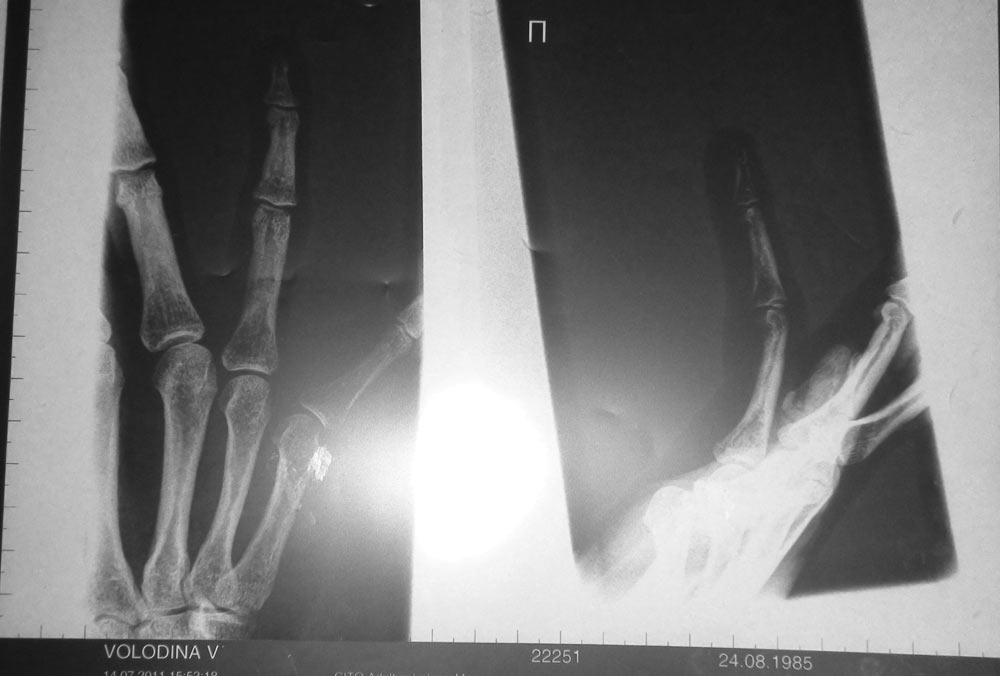

Была у Голубева на приеме в Цито. Из разговора поняла, что он такой "фигней" не занимается. У них там руки оторванные пришивают и тп. Кроме НПВП, опять же, и совета бросить спорт ничего не рекомендовал (сделали рентген, диагноз - синовит).